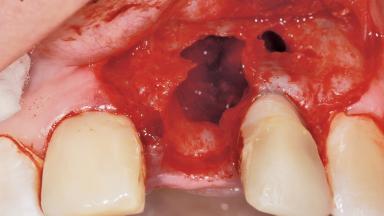

Late Placement of an Implant in a Maxillary Left Central Incisor Site

A 36-year-old female patient was referred for the replacement of the upper left central incisor (tooth 21), which had fractured. Although the tooth had been asymptomatic for many years, the crown began to loosen, at which time she presented to her dentist for an assessment. Teeth 21 and 22 had both been endodontically treated many years previously. She was a healthy individual and a non-smoker.

| Bone Augmentation | Horizontal|Staged |

| Augmentation Materials | Xenogenous|Membrane |

| Bone Volume | Deficient horizontally, requiring prior grafting |